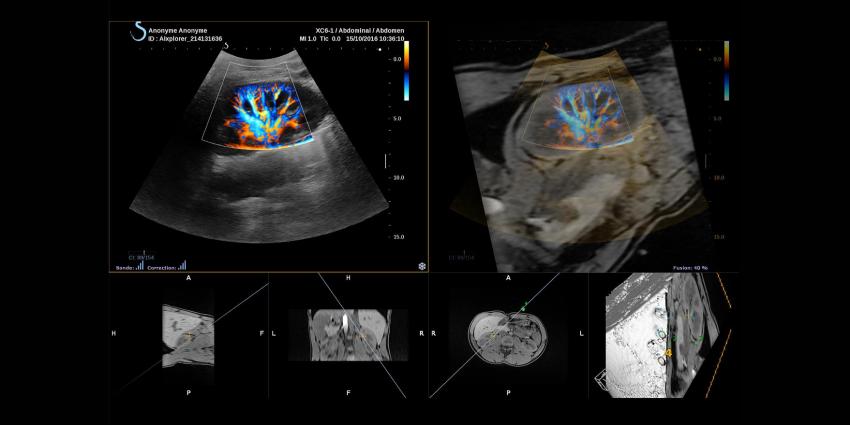

Aixplorer Ultimate — это разработка французской компании, которая уже на протяжении многих лет совершенствует и создает УЗИ аппараты нового поколения. Особенностью этого устройства считается использование новой технологии UltraFast, которая обеспечивает частоту кадра в 200 раз больше, чем у существующих ныне систем. Благодаря программной архитектуре, УЗИ аппарат может использовать улучшенные методы обработки изображений.

Высокое качество изображений обеспечивается программной технологией SuperFast от SuperSonic Imagine. Режим отображения играет очень большую роль в таких аппаратах, поэтому получаемая картинка должна быть однородной и четкой. Технология Tissue Tuner может адаптировать скорость ультразвука для нескольких органов, что расширяет возможности врачей в различных ситуациях.

Ну и конечно, дополнение ShearWave Elastography, которое также разработано этой французской компанией, позволяет визуализировать и оценивать жесткость тканей в режиме реального времени.

УЗИ сканер Aixplorer UltraFast позволяет врачам получать необходимое количество данных и открывает дверь к различным инновационным технологиям: